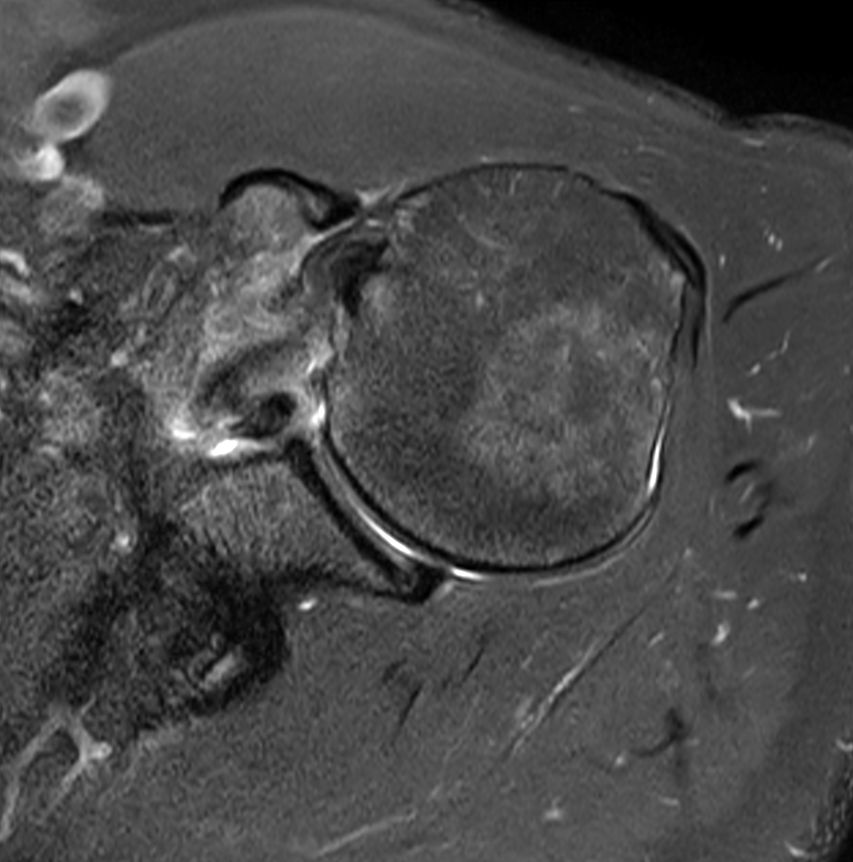

Shoulder with the dS Shoulder 16ch coil

University of Vermont Medical Center, Burlington, USA